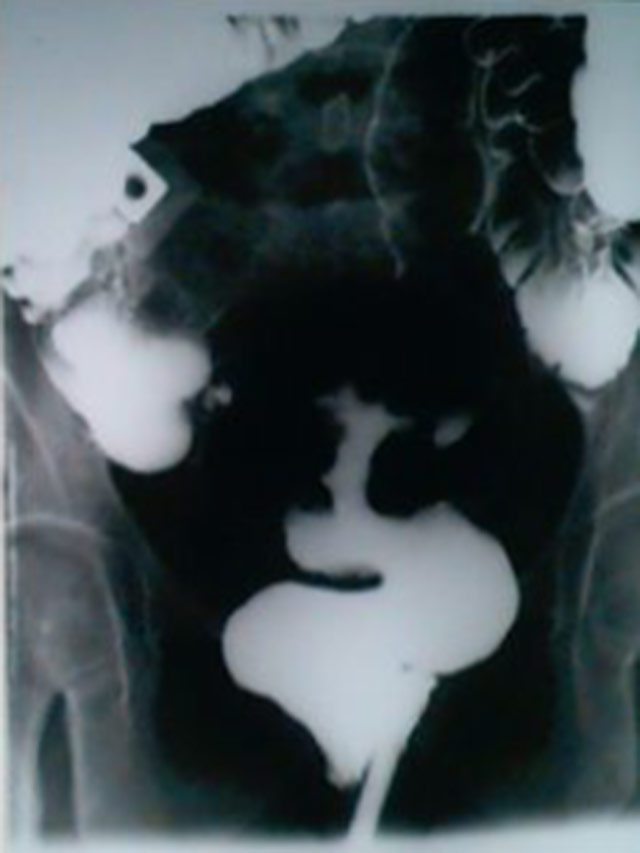

Radiografia de contrôle pós operatório para

avaliação da anastomose para fechamento da

colostomia. Vemos o contraste fluindo

em todo reto, colon ascendente e transverso

até a colostomia, enchendo a bôlsa.

No detalhe da bôlsa (pouco visível no slide)

vemos 2 áscaris no meio do contraste.